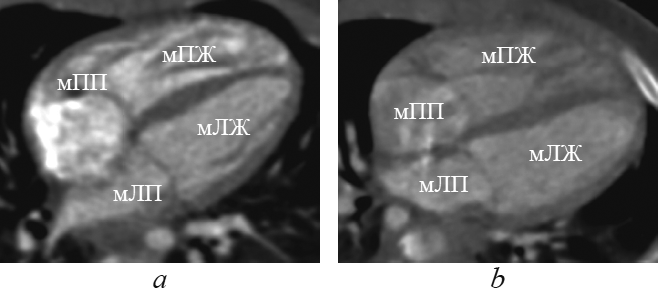

Рис. 3. Реформация приточных отделов желудочков. мЛЖ — морфологически левый желудочек; мЛП — морфологически левое предсердие; мПЖ — морфологически правый желудочек; мПП — морфологически правое предсердие

Fig. 3. Supply ventricles division reformation. мЛЖ – morphologically left ventricle; мЛП – morphologically leftatrium; мПЖ – morphologically right ventricle; мПП – morphologically rightatrium

При транспозиции магистральных артерий топология желудочков относительно расположения сердца в грудной полости следующая: морфологически правый желудочек располагается справа, спереди и снизу относительно морфологически левого желудочка (рис. 4).

Рис. 4. Реформация приточных отделов желудочков при транспозиции магистральных артерий. мЛЖ — морфологически левый желудочек; мЛП — морфологически левое предсердие; мПЖ — морфологически правый желудочек; мПП — морфологически правое предсердие

Fig. 4. Supply ventricles division reformation in great arteries transposition. мЛЖ – morphologically left ventricle; мЛП – morphologically left atrium; мПЖ – morphologically right ventricle; мПП – morphologically right atrium

При корригированной транспозиции магистральных артерий морфологически правый желудочек располагается слева и сзади от морфологически левого желудочка (рис. 5, 6).

Рис. 5. Реформация приточных отделов желудочков при корригированной транспозиции магистральных артерий. мЛЖ — морфологически левый желудочек; мЛП — морфологически левое предсердие; мПЖ — морфологически правый желудочек; мПП — морфологически правое предсердие

Fig. 5. Supply ventricles division reformation in corrected great arteries transposition. мЛЖ – morphologically left ventricle; мЛП – morphologically left atrium; мПЖ – morphologically right ventricle; мПП – morphologically right atrium

Рис. 6. Реформация приточных отделов желудочков при корригированной транспозиции магистральных артерий. мЛЖ — морфологически левый желудочек; мЛП — морфологически левое предсердие; мПЖ — морфологически правый желудочек; мПП — морфологически правое предсердие

Fig. 6. Supply ventricles division reformation in corrected great arteries transposition. мЛЖ — morphologically left ventricle; мЛП — morphologically left atrium; мПЖ — morphologically right ventricle; мПП — morphologically right atrium

При обычном расположении морфологически правое предсердие находится справа от морфологически левого предсердия. При обратном расположении морфологически правое предсердие находится слева от морфологически левого предсердия. Положение предсердий почти всегда связано с положением внутренних органов, но не зависит от положения желудочков или магистральных артерий. При транспозиции (см. рис. 4) и корригированной транспозиции (см. рис. 5, 6) взаимное расположение предсердий, как правило, обычное.